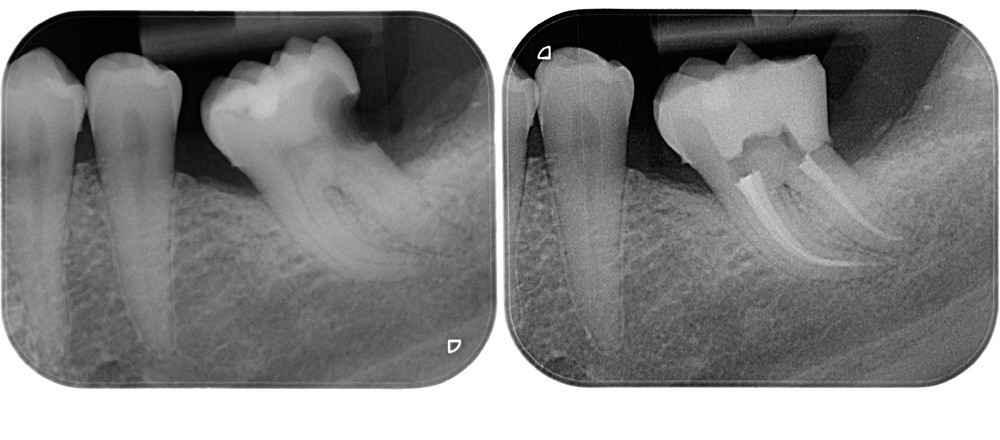

La condensation verticale à chaud est la technique d’obturation de référence. Elle nécessite de compacter la gutta-percha jusqu’à environ LT-4 mm avec un fouloir manuel. Avec les préparations conservatrices, il sera parfois difficile d’atteindre cette longueur, même avec le plus fin des fouloirs. Si on prend par exemple une préparation à 25/.04, le diamètre à LT-4 mm sera de 0,41 mm. Le fouloir le plus fin ayant un diamètre de 0,4 mm, il y a de forts risques de contact latéral avec les parois canalaires s’il atteint LT-4 mm, qui pourrait provoquer un effet de coin. Si le canal est courbe, il sera impossible d’amener le fouloir à la longueur souhaitée (fig. 17).

La condensation latérale à froid impose de pouvoir placer un spreader à LT-2 mm. Avec une préparation plus fine, il sera compliqué d’atteindre cette longueur, notamment s’il y a des courbures. C’est aussi une technique qui génère d’importants stress au niveau radiculaire, exposant la racine à un risque plus élevé de fracture [35]. Avec une préparation préservatrice, il y aura plus de contacts entre le spreader et la paroi dentinaire, et potentiellement une augmentation du risque de fracture (fig. 18).